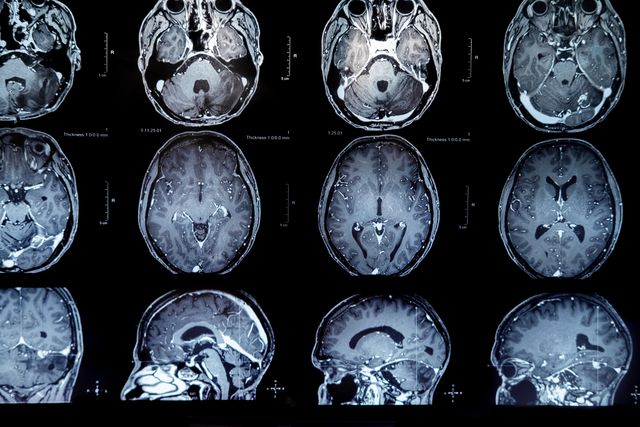

КТ ангиография сосудов головного мозга — это диагностический метод, который использует компьютерную томографию для получения детальных изображений кровеносных сосудов в области головного мозга. Этот метод позволяет визуализировать как артерии, так и вены, что помогает врачам выявлять различные патологии, такие как аневризмы, стенозы, тромбы или другие сосудистые аномалии. Процедура обычно включает введение контрастного вещества, что позволяет улучшить четкость изображений и обеспечить более точную оценку состояния сосудов. КТ ангиография применяется в различных клинических ситуациях, например, при подозрении на инсульт, травму головы или другие неврологические расстройства, и является важным инструментом для диагностики и планирования лечения.

Контрастное вещество во время сканирования позволяет наиболее точно увидеть все изменения в сосудах. Видна стенка, просвет, диаметр, наличие отложений. При опухолях головного мозга можно заметить аномальные разветвления — мальформации, питающие новообразование. Метод контраста достоверно показывает все сосуды церебрального бассейна.

В результате исследования врач получает трехмерное изображение сосудистой сетки головы и шеи. Некоторые участки специалист может записать в увеличении, они показаны на снимке отдельно. Информацию можно хранить как на диске, так и на пленочном носителе. К каждому исследованию предоставляется описание результатов от врача.